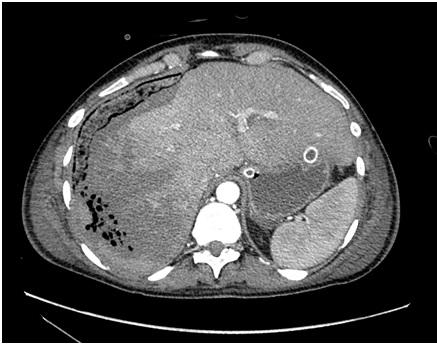

1. рис.1а мскт | |

2. рис1б мскт | |